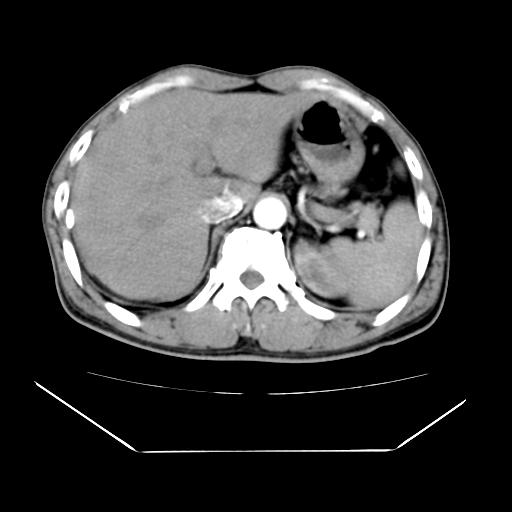

男性,55岁,外院体检afp明显升高,但b超未发现异常,否认乙肝病史。来我院ct增强。有延时扫描。

延时扫描完全充填,血管瘤

肝脏右叶动脉期可见低密度影,至延迟期被充填,考虑血管瘤可能性大。

肝右叶病灶

不排除肝右叶肝癌可能。

肝6段血管瘤

血管瘤可能性大。

考虑肝右静脉影。